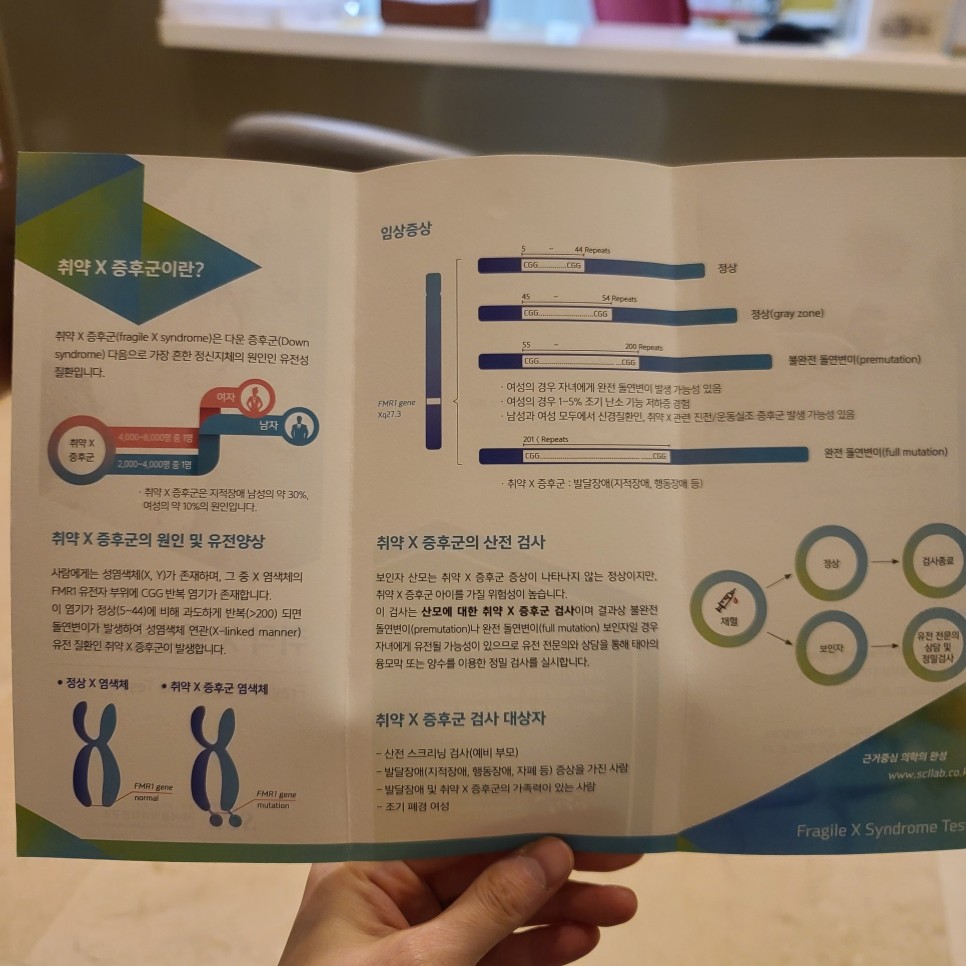

취약X증후군(Fragile Xsyndraome)이란 다운증후군 다음으로 가장 일반적인 정신지체의 원인인 유전성 질환이라고 합니다.

사람에게는 성염색체(X, Y)가 존재하고 그 중 X염색체의 FMR1 유전자 부위에 CGG 반복염기가 존재합니다. 이 염기가 정상(5~44)에 비해 과도하게 반복(>200)되면 돌연변이가 발생하고 성염색체 관련 유전질환인 취약X증후군이 발생합니다.

취약X증후군은 발달장애(지적장애, 행동장애 등)의 원인이 되는데 지적장애 남성의 약 30%, 여성의 약 10%의 원인이라고 합니다. (※취약X증후군 리플릿 참고)

임신 주수에 관계없이 검사 가능, 임신마다 하지 않아도 됩니다(1회 검사로 종료) 취약X증후군 검사로 99% 이상 진단이 가능하므로 산전 아이의 발달장애 여부를 미리 예측할 수 있습니다. 임신 주수에 관계없이 언제 검사해도 상관없고, 1회 검사하면 임신할 때마다 하지 않아도 된다고 합니다.